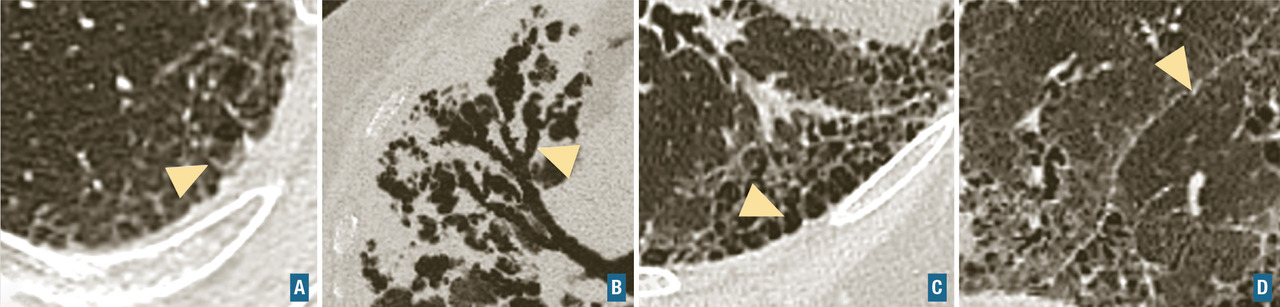

L’aspect scannographique rencontré au cours de la sarcoïdose est décrit dans la fig. 6.